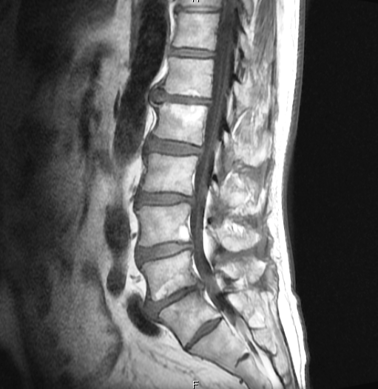

脊柱管狭窄症

主訴 腰の痛み・左下肢の痺れ

腰椎全体の狭小(特にL1/2・L5/S1)・右仙腸関節・上部頸椎・椎骨動脈・腰椎減圧・スーパーライザーにてヘルニア該当部位への組織の治癒過程の促進,炎症の鎮静や微細循環の促進,浮腫の改善・呼吸促進による細胞への酸素供給・キネシオテープ・強直性脊椎骨増殖症の疑い

初診時の印象は、脊柱管狭窄・椎間板変性・骨感染や転移の疑い・頸椎の変形による椎骨動脈の血流不全などの疑いなどがあり、症状も強く、率直なところ、どこまで改善できて時間がかかるか若干不安があったが、根気よく通院してくだされば良い結果につながると強く感じました。